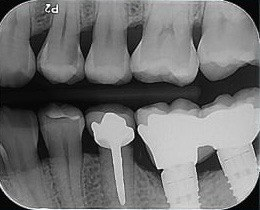

1. What option can be selected regarding the implant seen in this X ray?